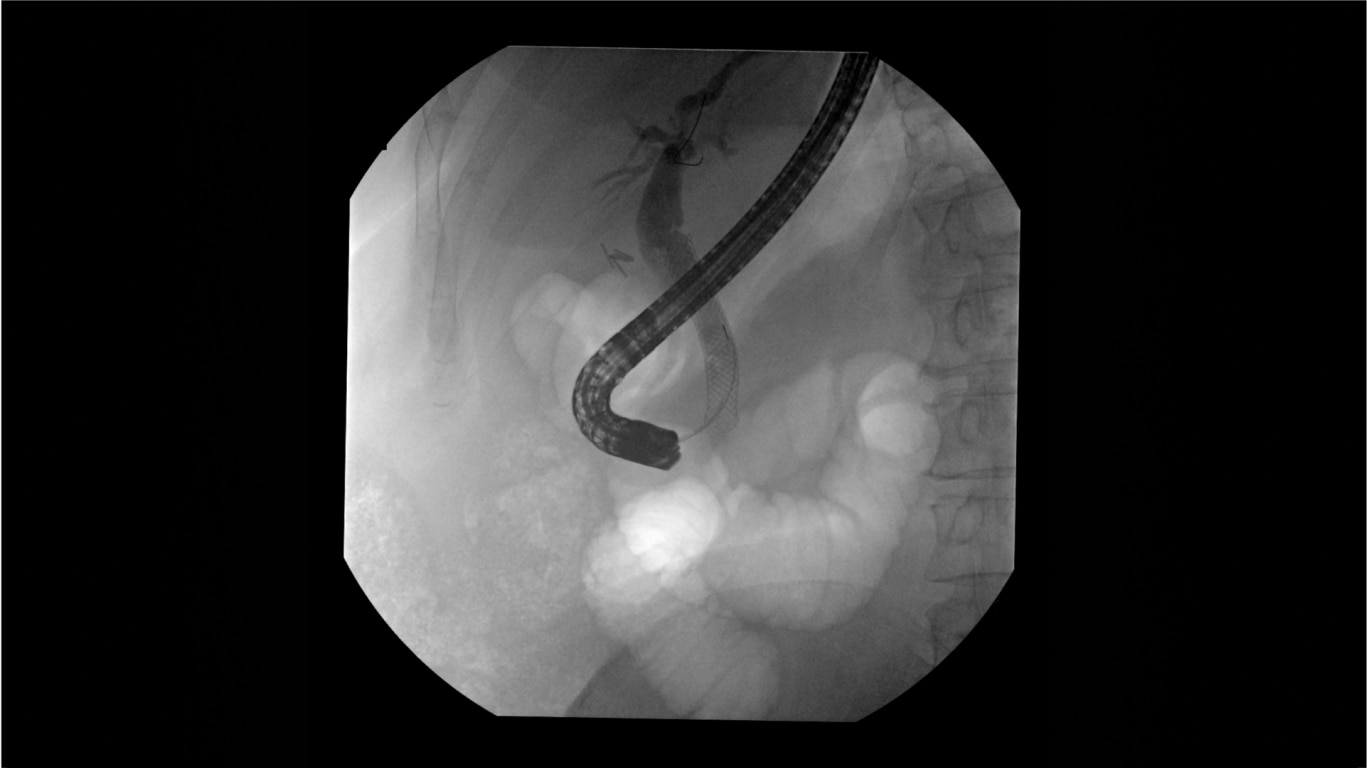

Clearly visualize the GI tract of patients, regardless of size, during a wide range of endoscopic procedures, including ERCP. OEC C-arms offer amazing image quality at low dose and provide enhancements for clear visualization during movement in soft tissue, such as during guidance of low-density drainage tubes or thin biopsy brushes. A large, clear display with comfortable viewing enables effortless workflow.

See detail 1 for 1 from detector to a 4K UHD display for stunning image quality and visualization of low density drainage tubes and thin biopsy brushes.

Live Zoom up to 4X during a fluoro or Cine without the additional dose of Mag modes or resulting X-ray tube heat buildup to see guidewires or tubes during procedures.

Capture up to 22% more Field of View by positioning the OEC Elite detector closer to patient anatomy with the OEC low-profile X-ray tube housing compared to mono-block C-arms.

Complex gastrointestinal procedures require powerful imaging systems. OEC premium C-arms perform in a variety of procedures such as:

• Endoscopic retrograde cholangiopancreatography